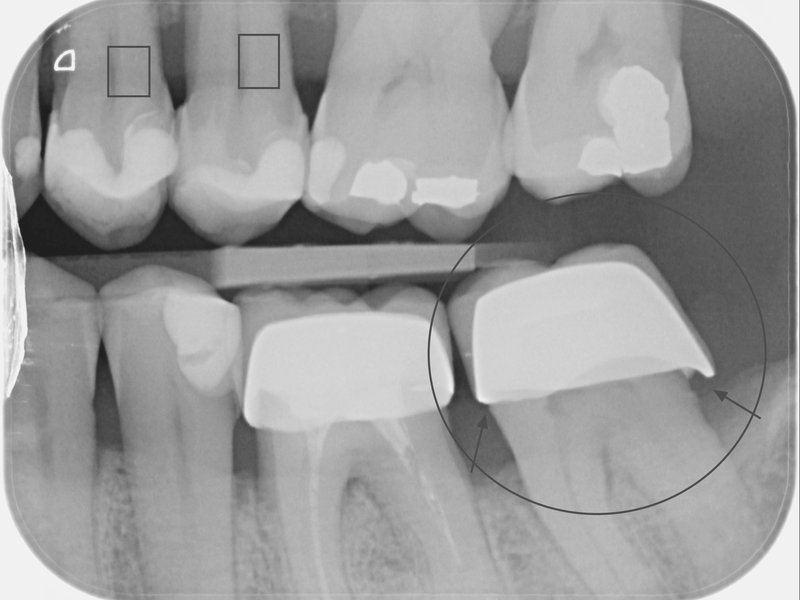

Srovnání přesné korunky (vlevo) a nepřesné korunky (vpravo)

Nepřesná korunka